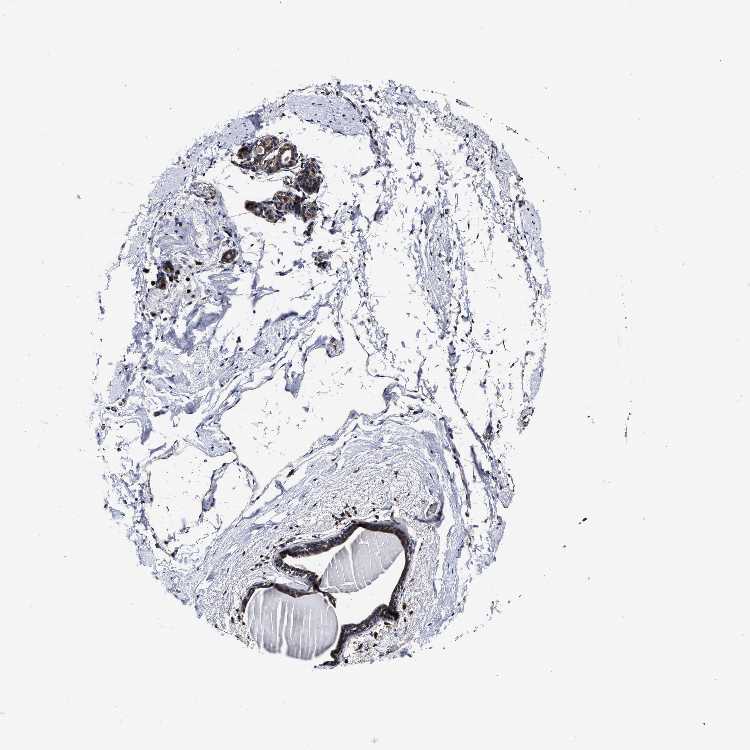

BREAST - Antibody stainingi

Antibody staining in the annotated cell types in the current human tissue is reported as not detected, low, medium, or high, based on conventional immunohistochemistry profiling in selected tissues. This score is based on the combination of the staining intensity and fraction of stained cells.

Each image is clickable and will lead to virtual microscopy that enables deeper exploration of all samples and also displays staining intensity scores, fraction scores and subcellular localization as well as patient and tissue information for each sample.

Antibody HPA020863

Adipocytes Medium

Glandular cells Medium

Myoepithelial cells Low